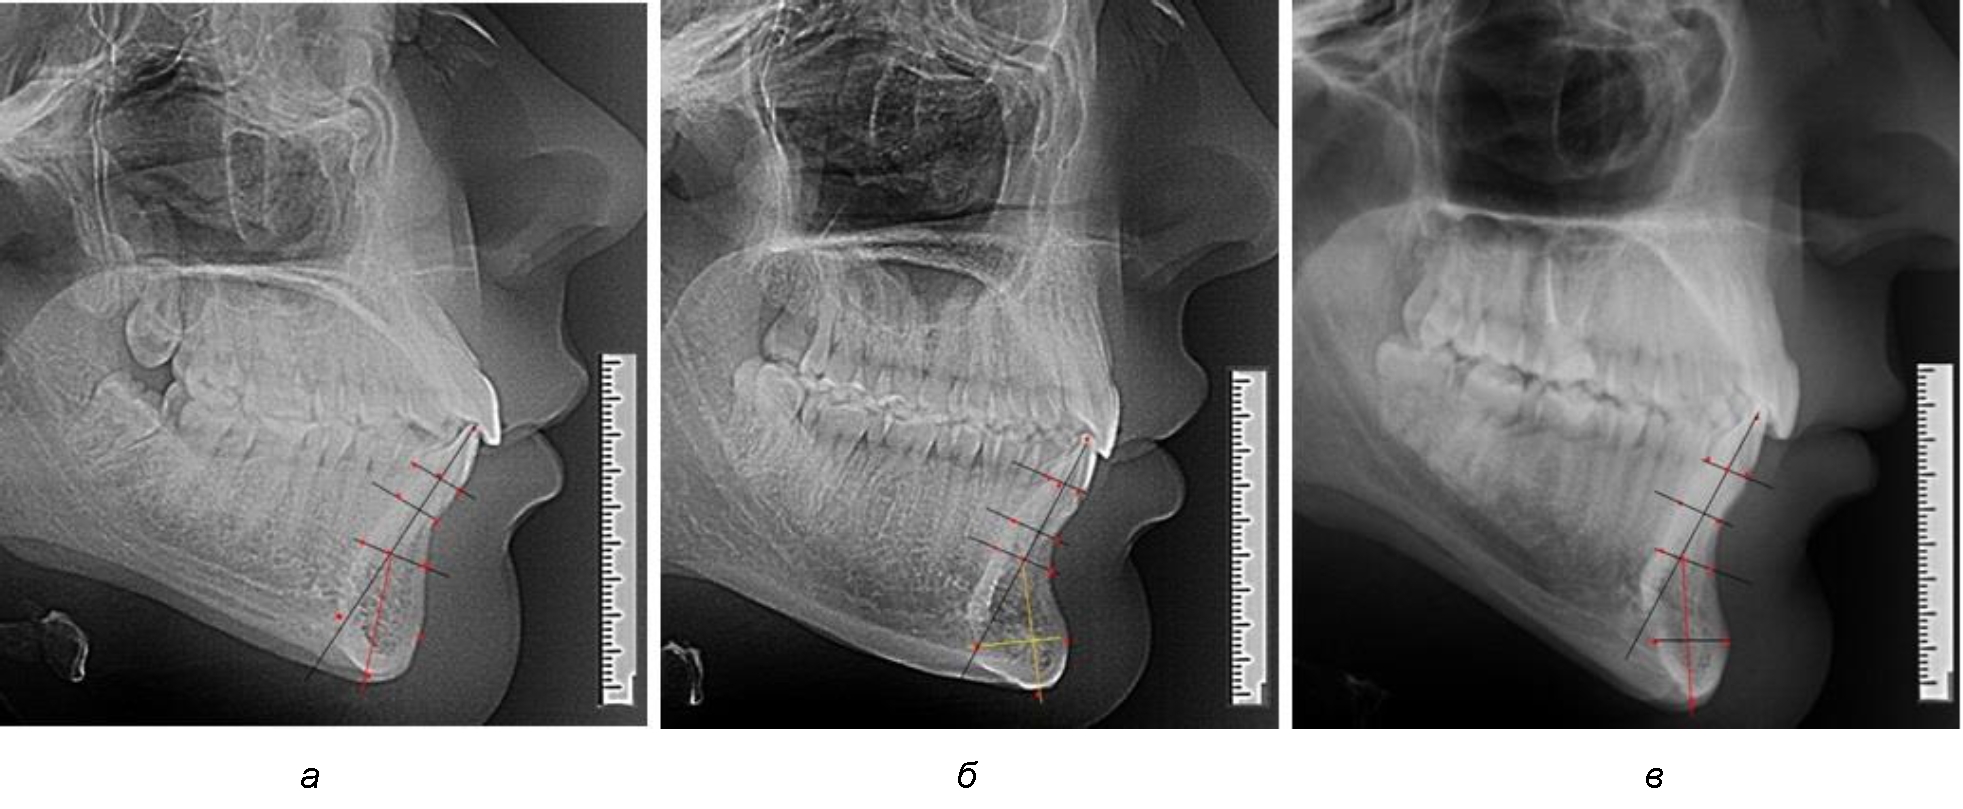

При анализе полученных данных обращает на себя внимание факт того, что из вертикальных параметров зубоальвеолярной части сегмента наиболее вариабельным является размер между апикальными точками Downs и Schwarz (BSM–B), который составлял (6,79 ± 0,54) мм, при величине сигмального отклонения – 2,35. Также большая ошибка репрезентативности и сигмальное отклонение было отмечено при оценки ширины подбородочного выступа. В связи с этим встречались варианты резцовых сегментов нижней челюсти различные как по ширине, так и по высоте, а также по расхождению положения апикальных точек по Downs и Schwarz (рис. 3).

Рис. 3. Варианты среднего (а), широкого (б) и узкого (в) нижнечелюстного резцового сегмента

Так же, как и при исследовании сегментов, обращает на себя внимание факт того, что из вертикальных параметров зубоальвеолярной части сегмента наиболее вариабельным является размер между апикальными точками Downs и Schwarz (BSM–B), который составлял (6,79 ± 0,41) мм, при величине сигмального отклонения 1,78.

Также большая ошибка репрезентативности и сигмальное отклонение было отмечено при оценке ширины подбородочного выступа.

Варианты резцовых сегментов нижней челюсти различные как по ширине, так и по высоте, а также по расхождению положения апикальных точек по Downs и Schwarz представлены на рис. 4.

Рис. 4. Особенности нижнечелюстного резцового сегмента на ТРГ у людей при среднем (а), широком (б) и узком (в) вариантах

Типологические варианты подбородочного выступа, различающиеся по ширине, высоте и расположению апикальных точек, необходимо учитывать в клинике ортодонтии при проведении диагностических мероприятий. Протокольные точки для построения эстетических линий, исходящие из выступающей точки подбородка (Рog – погонион), не всегда могут быть объективным критерием диагностики, что объясняется различной выпуклостью переднего отдела подбородочного выступа. Точки апикального базиса по Шварцу и Даунсу находятся в различных местах подбородка и не всегда совпадают, что требует пояснения при выборе ориентиров. Кроме того, вариабельность сагиттальных размеров зубоальвеолярной части резцового сегмента позволит опти-мизировать методы перемещения резцов в переднее-заднем направлении и определяют костный биотип альвеолярной части нижней челюсти в анализируемой области.

При аномалиях окклюзии в сагиттальном направлении и характерных для них различных вариантах протрузионного и/или ретрузионного патологического положения передних зубов, как правило, сопровождается изменениями параметров подбородочного выступа. Учитывая многообразие форм аномалий окклюзии, параметры подбородочного выступа вариабельны как по сагиттали, так и по трансверсали.

Нередко отмечается деформация подбородочного выступа и различное его положение по отношению к зубоальвеолярной части сегмента. При мезиальной окклюзии нередко нижняя подбородочная точка смещается кзади по отношению к условной срединной вертикали нижнего резца, а при дистальной окклюзии отмечается компенсаторное отклонение подбородка кпереди (рис. 5).

Рис. 5. Особенности нижнечелюстного резцового сегмента на ТРГ у людей при мезиальной (а) и дистальной (б) окклюзии

Кроме того, так же как и у людей с физиологической окклюзией, определялось различие в положении апикальных точек Downs и Schwarz, что, по нашему мнению, может определять тактику лечения патологических форм протрузии/ретрузии резцов с учетом биотипа костной ткани.